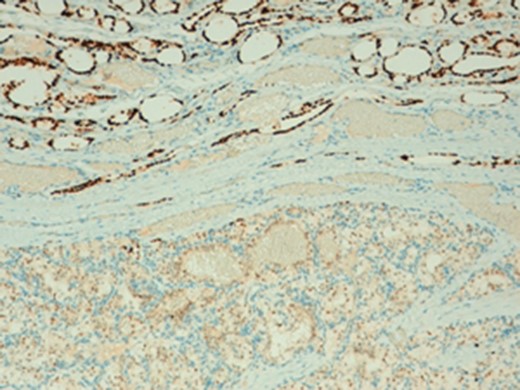

The histologic diagnosis was aided by the use of immunohistochemistry which was positive for PAX8 (Fig. 4) and CD10, and negative for thyroid transcription factor 1 (TTF-1) (Fig. 5), vimentin and chromogranin.

Importantly, the differential diagnostic consideration of a metastatic clear cell carcinoma within the clear cell parathyroid gland parenchyma may prove challenging since both tumors could be PAX8 and RCC immunoreactive [8,9]. However, a positive reaction with CAIX and CD10 and a negative reaction with chromogranin and parathyroid hormone studies can help confirm a RCC origin [4,9].